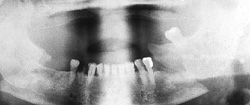

The primary purpose of the consultation is the outpatient follow-up treatment and care of patients who have undergone surgery following bone injuries to the upper and/or lower jaw. In addition to patients with fractures of the facial skull, patients with injuries to the teeth and facial soft tissues are also followed up.

Osteosynthesis procedures are performed at our clinic according to modern international standards. Mini and micro plates made of titanium and special medical steel are used to stabilize the fractured bones. Especially for the treatment of temporomandibular joint fractures a joint plate was developed in our clinic. The development and application of resorbable osteosynthesis materials is at the same time a research task of the clinic.